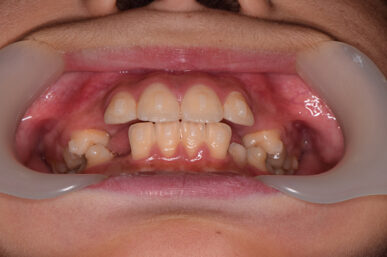

• Before

治療の開始が遅く、犬歯と奥歯の生え代わりが始まっていましたが、床矯正より治療スピードが早いアライナー矯正を使用して、犬歯のスペースをとても短期間に作ることができました。八重歯を防げましたので固定式の装置は必要なくなりました。永久歯がすべて生えるまでは予防歯科で歯の生え代わりと機能を管理します。